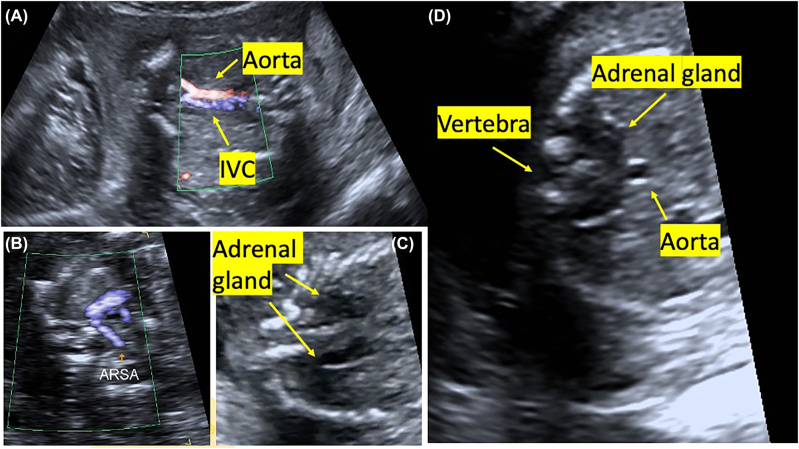

Case presentation: We report a case of bilateral renal agenesis diagnosed prenatally. We presented the ultrasound and pathology images of this fetus with a new sonographic sign, segmental anterior deviation in the abdominal aorta.

Conclusions: To our knowledge, this is the first reported case of a fetus with a segmental aortic anterior deviation.